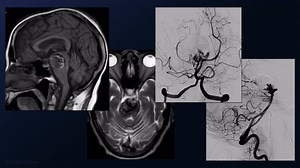

Giant MCA Aneurysm | Cohen Collection | Volumes | The Neuros

#499: Combined EC-IC and IC-IC Double Bypass with Proximal Clip

#493: STA-M2 MCA Bypass and Clip Reconstruction of a Giant Middle

#477: Orbitozygomatic Craniotomy and Transcavernous Approach fo

#215: Recurrent Giant Basilar Apex Aneurysm after Coiling and Flow

#227: Clip Reconstruction of a Recurrent Giant M2 MCA Aneurys

#141: Treatment of a Giant, Dolichoectatic, Thrombotic Superi

Clipping Of the Giant Aneurysm Of The Posterior Communicating Art

#471: Thrombectomy and Clip Reconstruction of a Giant, Throm

#55: Fourth-Generation M2 (S-E) RAG (E-S) S2 Bypass and Proxima